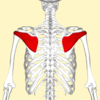

Which Muscle is This?

Deltoid